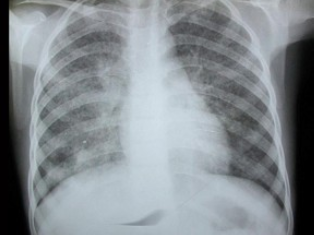

7、单项选择题

男,48岁,常感胸闷气逼,近1月渐加重,X线检查如图,最可能的诊断是()

A.右侧气胸

B.右侧肺大泡

C.两肺肺大泡

D.正常胸片

E.肺气肿